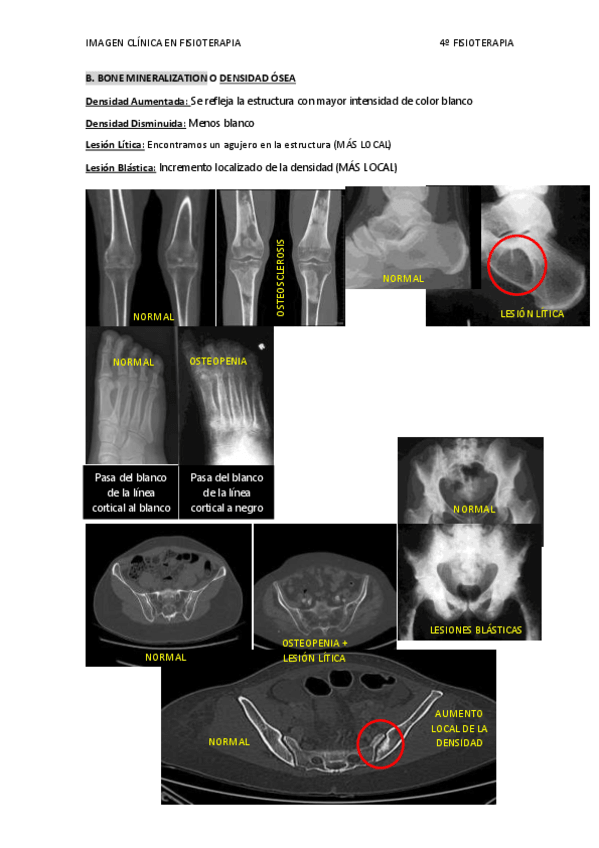

He publicado nuevos apuntes de 4º IMAGEN CLÍNICA EN FISIOTERAPIA: TEMA 5.pdf

5 páginas